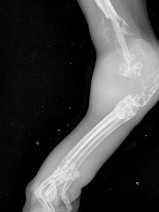

• 14ème Cours de Propédeutique, sémiologie et pathologie de l'appareil locomoteur : les complications en pathologie articulaire

L'objectif pédagogique de ce cours avancé est de renforcer les connaissances en pathologie ostéo-articulaire chez le chien et le chat. Des mises au point concernant les connaissances les plus récentes seront réalisées cette année sur les complications rencontrées en pathologies ostéo-articulaires. L'accent sera toujours mis sur le côté pratique et visuel. Un temps important sera consacré à la d...

Du 9 au 12 juin 2021

Bédoin (84410)

Orthopédie

G.E.C.O.V.